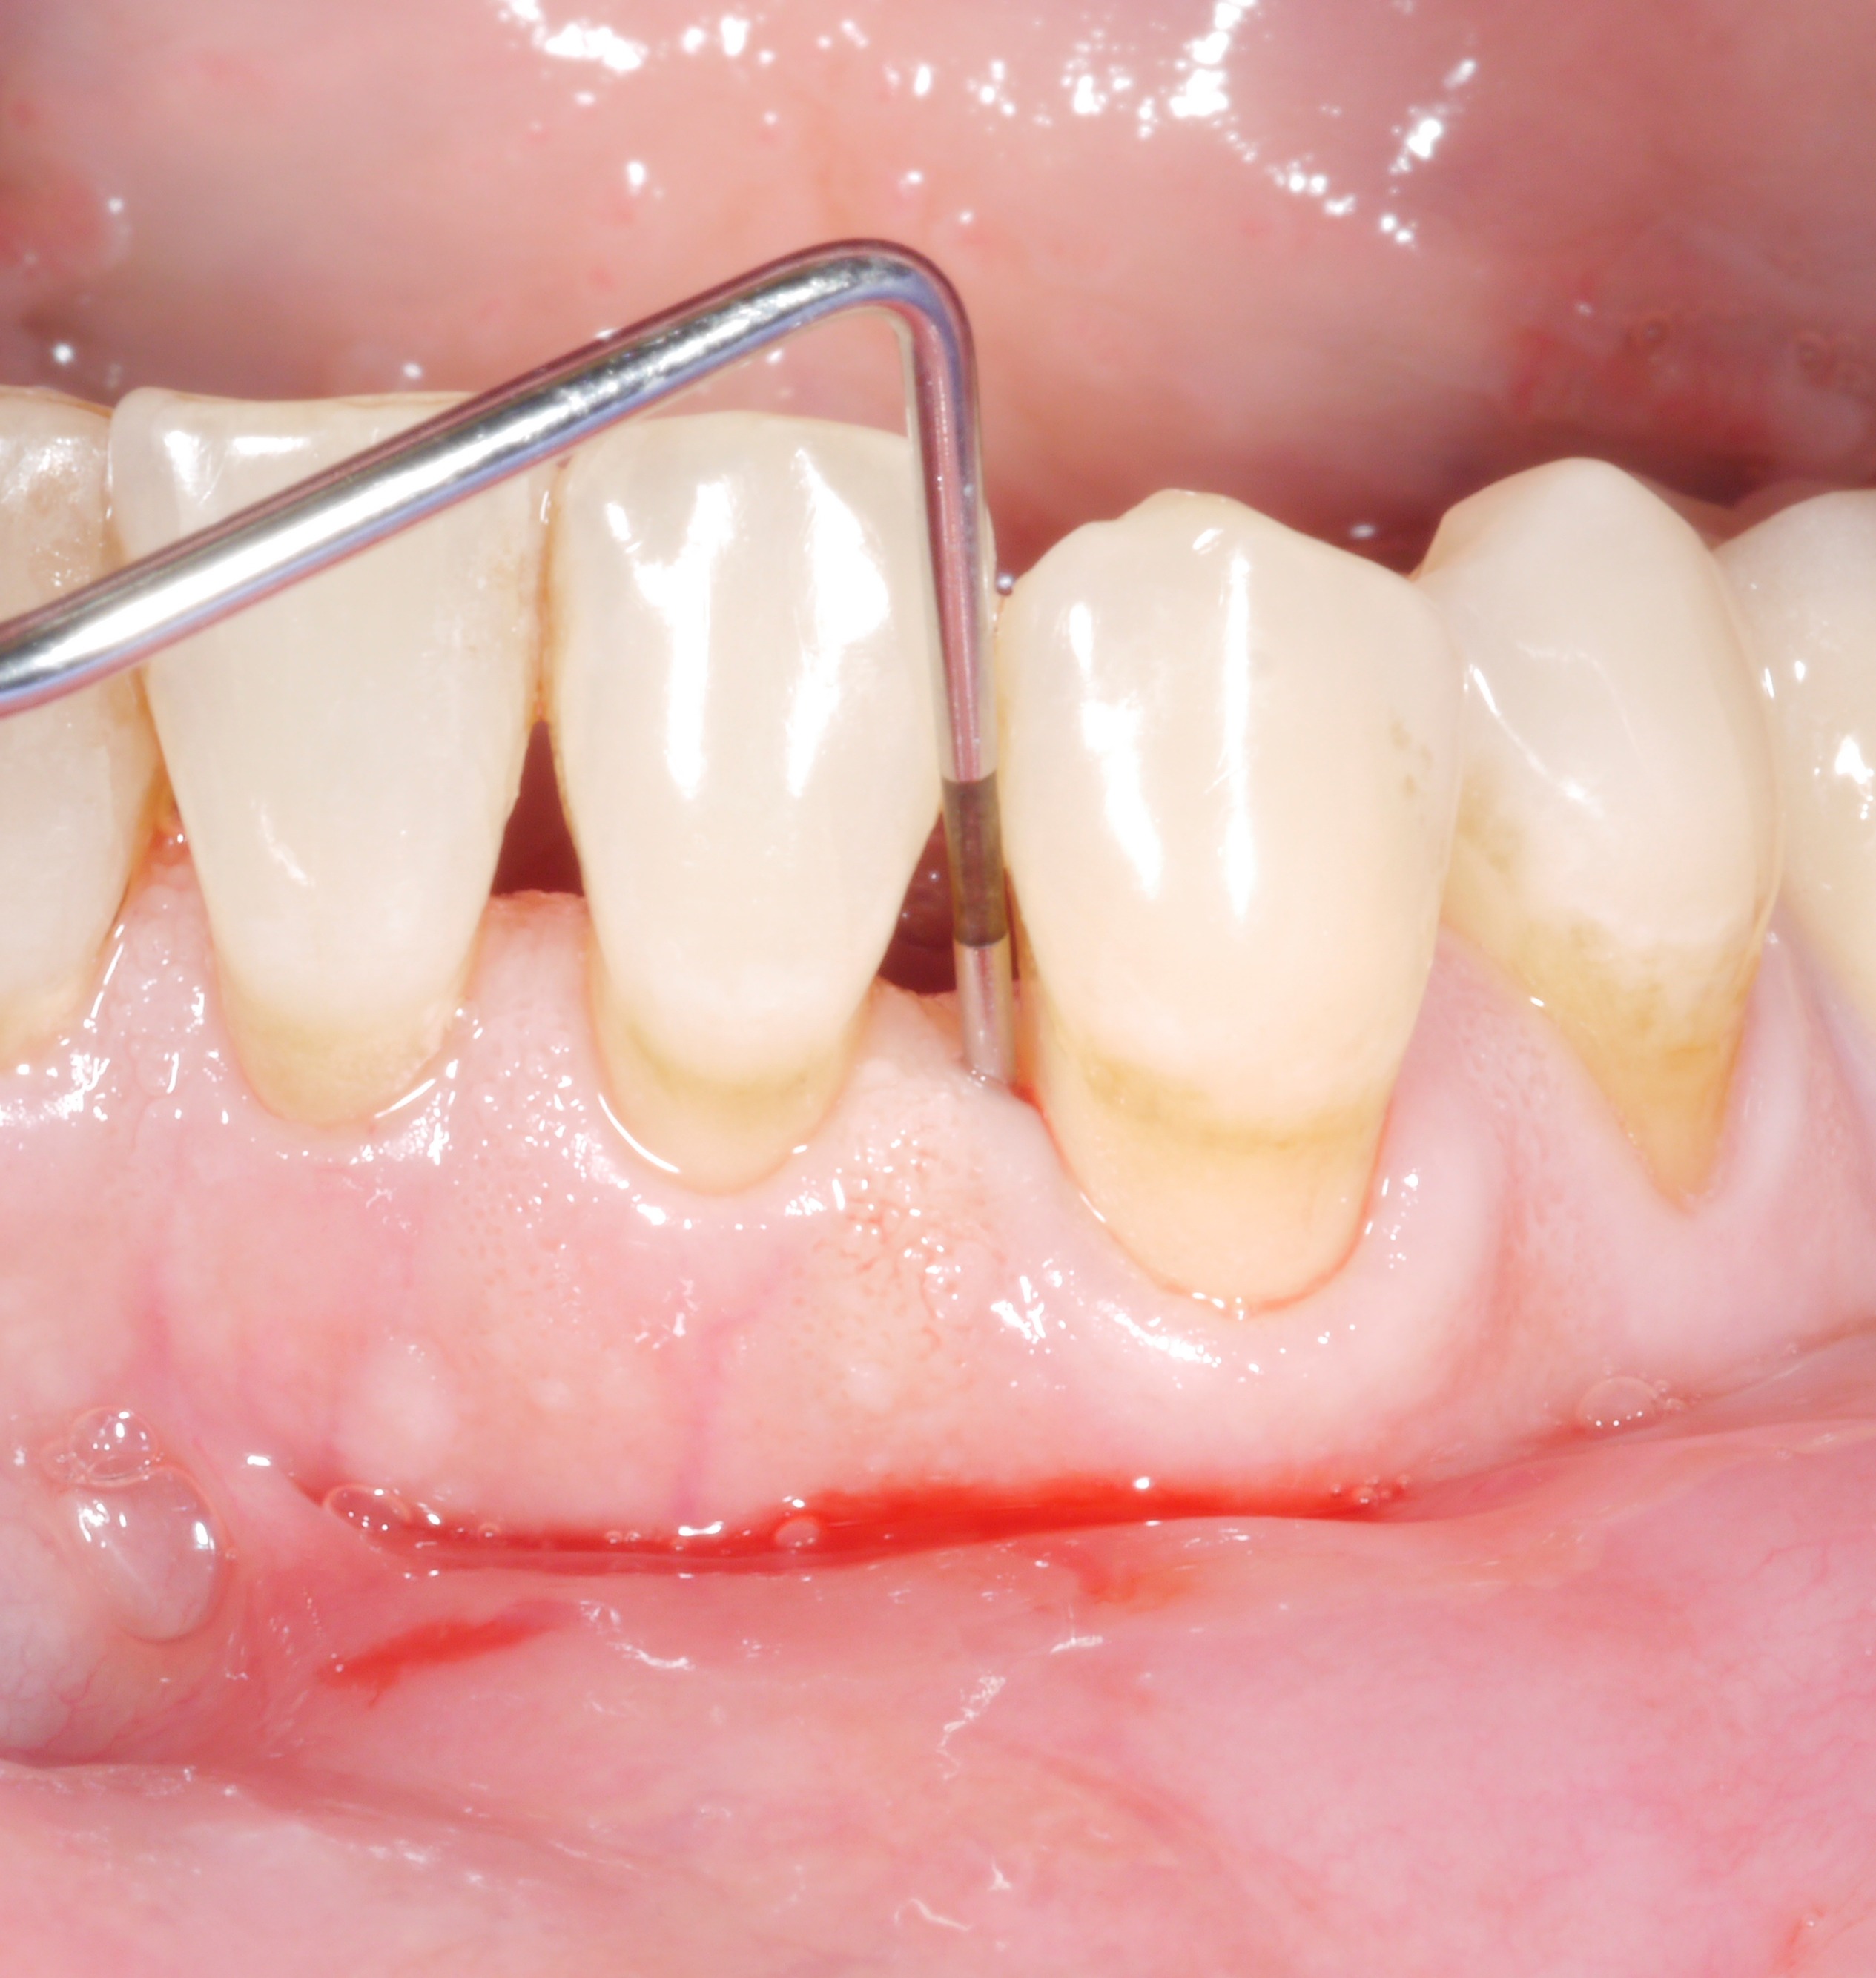

Това е ситуация, която ни е добре позната: след активната фаза на лечението почти всички зъби на пациента вече не са засегнати от увеличените дълбочини на сондиране. Въпреки това все още има 1 или 2 места, където целта на лечението за съжаление не е постигната. Възможно е да възникне следната мисъл: „Колко лошо може да бъде това? Един единствен джоб с 6 или 7 мм - със сигурност това не може да има голямо значение?“

Денталните лекари обаче не трябва да се задоволят твърде бързо с оставащите дълбочини на сондиране по-големи от 4 mm, защото те представляват проблем, поне в дългосрочен план - както за засегнатия зъб, така и за останалото съзъбие.

• Кървенето при сондиране удвоява риска от по-късна загуба на зъби.